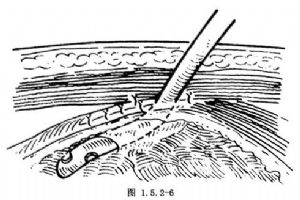

切口及显露手术野的步骤与荷包式胃造口术相同。胃造口部位应选择在胃前壁偏右侧,用不吸收线做一荷包缝合,于其中央切开胃壁,用导尿管经此切口插入胃腔并收紧结扎荷包缝合线(图1.5.2-4)按照胃的纵轴方向,沿导管两侧做胃壁浆肌层缝合,将导管包埋于浆肌层缝合的隧道中,长度约4~5cm(图1.5.2-5)。将导管从切口左侧腹壁的戳口拖出、沿导管四周的胃壁与腹膜缝合固定3或4针使造口处胃壁紧贴腹壁。最后将导管与皮肤固定并缝合切口(图1.5.2-6)。